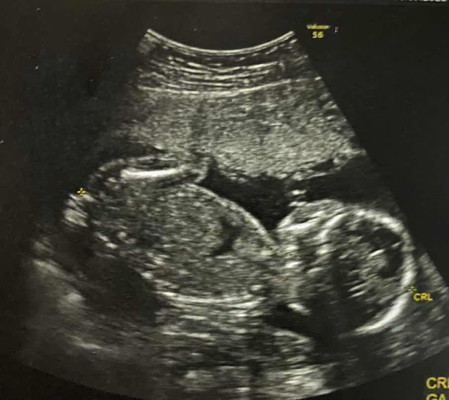

ไปพบคุณหมอตอน20w ตรวจพบแคลเซียมเกาะหัวใจ แม่นี่เครียดเลยค่ะ มันเกิดจากสาเหตุอะไรหรอคะ หมอนัดตรวจอีกทีวันที่15😞😞

VIP Parentsไปพบคุณหมอตอน20w ตรวจพบแคลเซียมเกาะหัวใจ แม่นี่เครียดเลยค่ะ มันเกิดจากสาเหตุอะไรหรอคะ หมอนัดตรวจอีกทีวันที่15😞😞